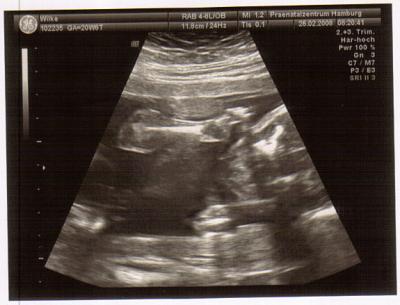

Die Bilder sind leider nicht doll, aber ich stelle trotzdem 2 rein. Hier einmal von vorne mit Hände hoch :o)